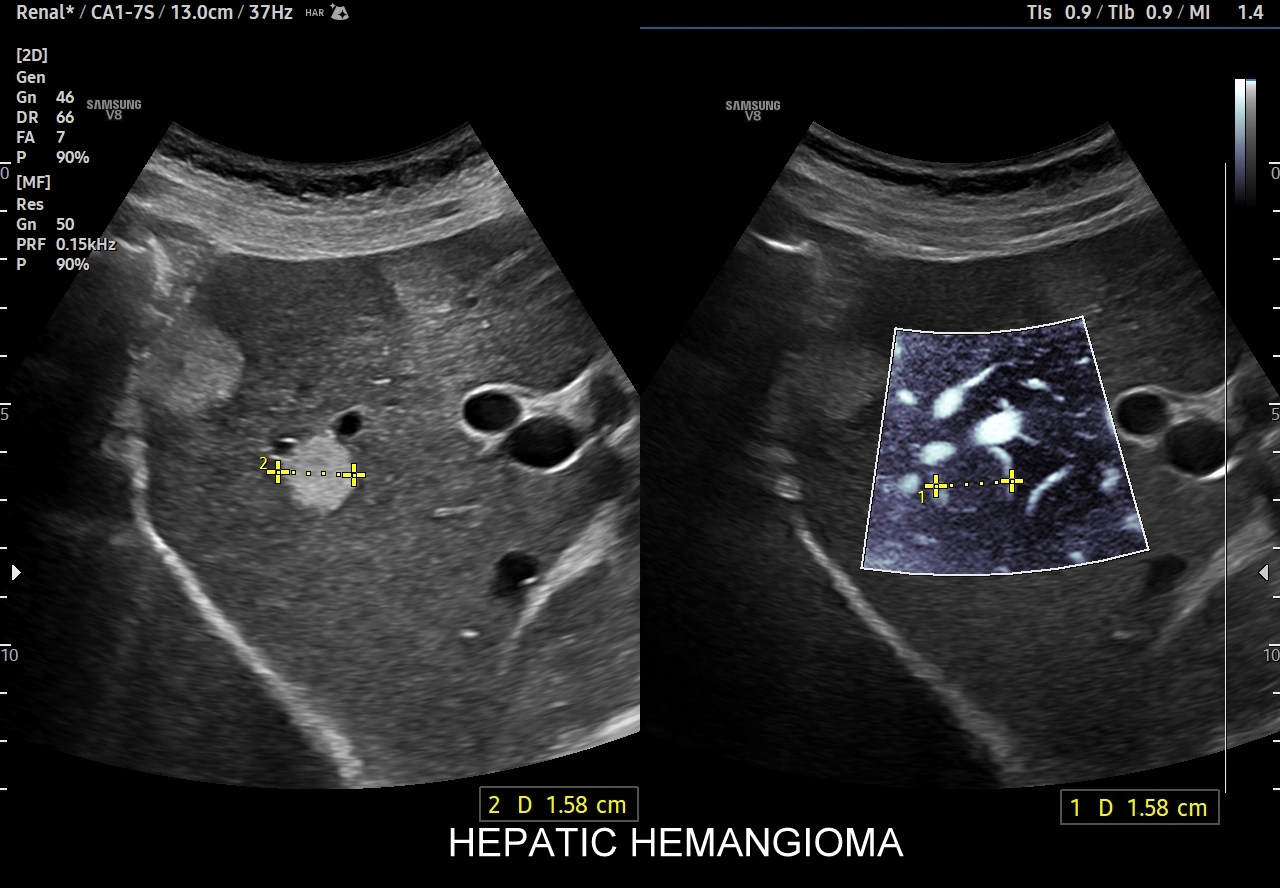

W badaniu USG w prezentacji B w niestłuszczonej wątrobie typowy naczyniak włośniczkowy lokalizuje się w pobliżu gałęzi żyły wątrobowej, a prezentuje się jako ostrookonturowana, hyperechogenna, jednorodna, krągła lub owalna zmiana ogniskowa. Ze względu na niską prędkość przepływu krwi i wynikające z tego ograniczenie detekcji w trybie color-Doppler w naczyniaku nie rejestruje się sygnału. Z kolei w trybie mikrounaczynienia (MVI / MVF) w zależności od czułości aparatury w naczyniaku można zaobserwować delikatny sygnał w postaci „poprószonego śniegu”.

Naczyniaki duże, tj. powyżej 2-3 cm, mogą mieć strukturę niejednorodną echogenicznie, w tym obszary hypoechogenne. Spotyka się także naczyniaki o charakterystyce normo- lub hypechogenicznej, w szczególności w wątrobie stłuszczonej. Z powyższych względów należy mieć na uwadze i zapamiętać, że badanie USG w podstawowym trybie B nie jest wystarczające do postawienia rozpoznania naczyniaka wątroby. W ramach obrazowej diagnostyki różnicowej najbardziej pomocnym jest badanie USG z kontrastem (CEUS), w którym to naczyniak wątroby posiada charakterystyczny wzorzec wypełnienia.